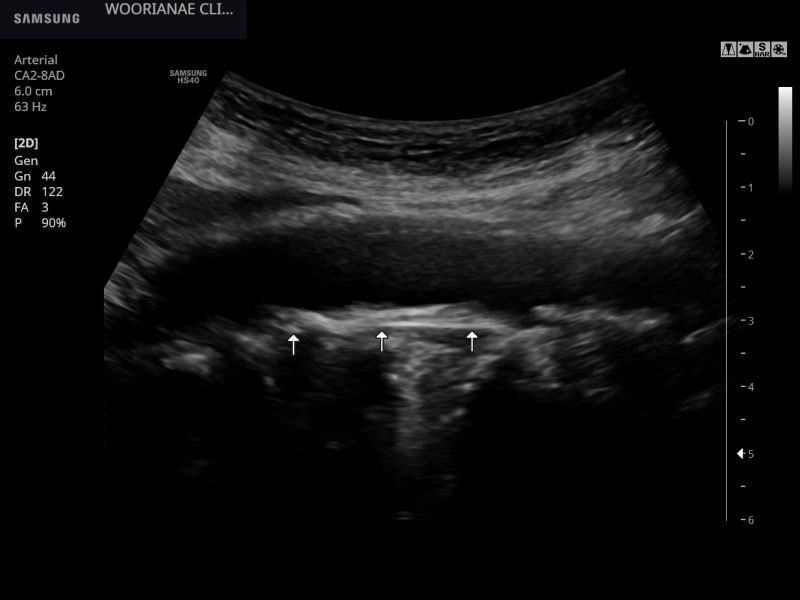

대동맥의 비틀림 등을 제거하기 위해 혈관도 관찰하는데… 명확한 동맥경화, 플라크(plaques)가 관찰된다; 20대부터 흡연력

비틀림형 확장 소견(aneurys malchange)은 없었으며 동맥 주변에 저음영 이상 소견은 관찰되지 않았다.